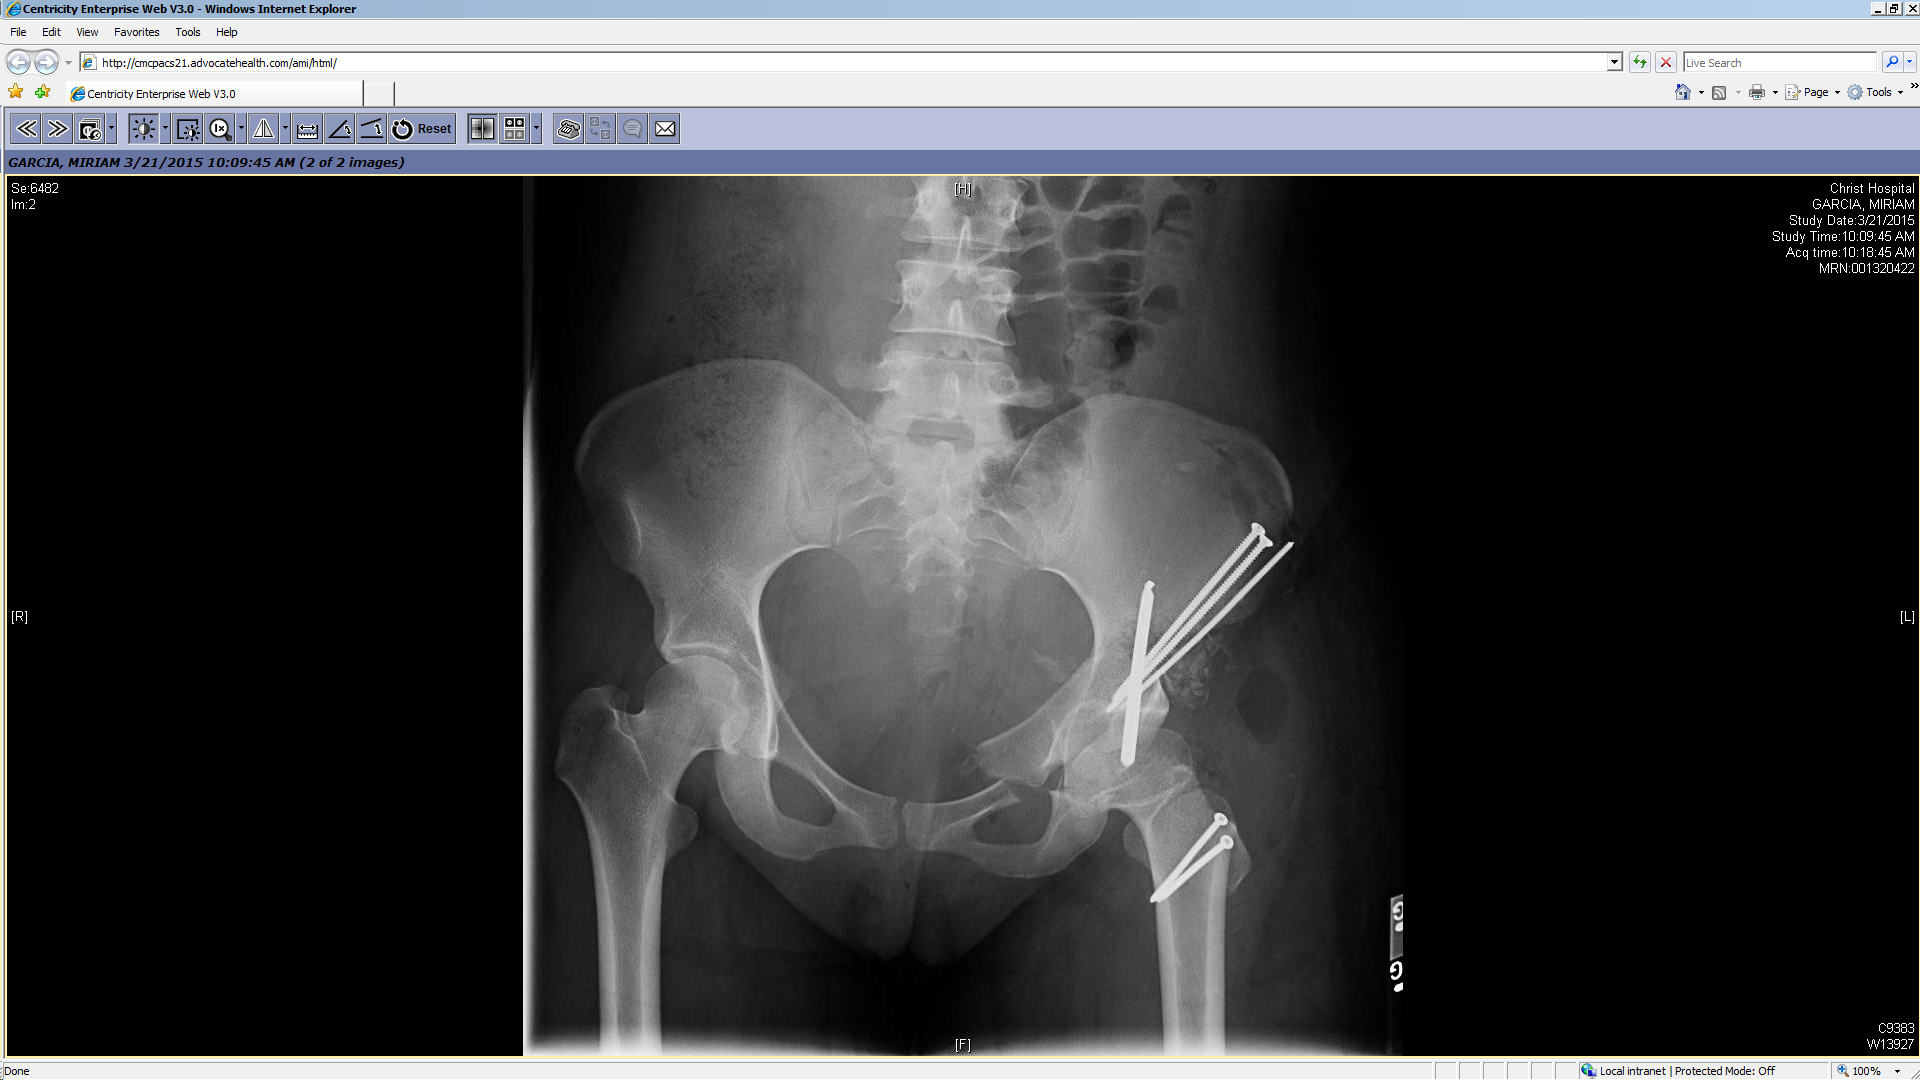

Treatment

Treatment can be selective — identifying and treating the most likely cause of hip pain and dysfunction — or comprehensive, correcting all potential causes in one stage. Dr. Prasad Gourineni performs arthroscopic evaluation and correction of mild asphericity of the head or acetabular retroversion when the remaining morphological variations are mild and unlikely to cause symptoms. In more severe deformities, all abnormalities are corrected with the surgical dislocation approach, which allows head reshaping, neck lengthening, greater trochanter transfer, and acetabuloplasty.